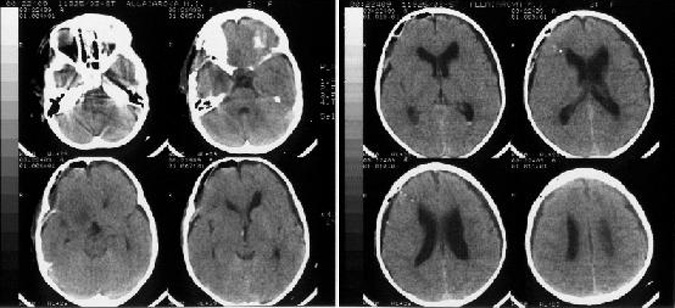

В 3 сутки была снижена доза дексаметазона до 2 мг/сут, гидрокортизон и Л-тироксин в прежней дозе, минирин введен 1 раз в дозе 1 мг.4 сутки после операции. Состояние больной ухудшилось, отмечалось нарушение сознания до сопора - комы, остро развился генерализованный судорожный припадок: клонические сокращения мимической мускулатуры левой половины лица, тризм жевательной мускулатуры, тонические судороги в конечностях по типу децеребрации. При КТ исследовании головного мозга было выявлено (рисунок 2): равномерное скопление ликвора субдурально с обеих сторон, уменьшение размеров желудочковой системы по сравнению с 1 сутками. В течение суток отмечалось еще 4 генерализованных судорожных припадка. Выявлялась устойчивая гипертермия до 39ºС.

В течение суток отмечалось несколько эпизодов снижения артериального давления до 75/40 мм.рт.ст., выявлялась устойчивая тахикардия до 130 – 140 / мин., ЦВД было повышеным до 12 - 15 см.вод.ст. Перистальтика кишечника была значительно ослаблена. Отмечалось снижение темпа диуреза, в динамике снизился уровень натрия плазмы крови (см. Таблицу 2).5 сутки после операции. Сохранялось коматозное состояние (кома I). Судорожные припадки не повторялись. Выявлялись эпизоды стереотипного двигательного беспокойства, повышение мышечного тонуса по пластическому типу. Усугубился орально-стволовый синдром (угнетение фотореакции, зрачки симметричные узкие, низкие роговичные рефлексы, парез рефлекторного взора вверх). При транскраниальном допплерографическом исследовании: отмечалось повышение линейной скорости кровотока (ЛСК): в фазу систолы до 194 см/сек, в фазу диастолы до 122 см/сек, средняя до 152 см/сек, в бассейне средней мозговой артерии (СМА) справа, что было расценено, как умеренный ангиоспазм.

В суточной моче было повышено содержание Na (Na 600 ммоль/сут), показатели креатинина, мочевины в плазме крови оставались в пределах нормы. Отмечалось снижение уровня кортизола в крови 90 нмоль/л (нормы 260 - 720 нмоль/л), Т3 - 0,3 нмоль/л (норма 0,9 - 2,9 нмоль/л), Т4 – 20 нмоль/л (норма 58 - 142 нмоль/л).6 сутки после операции. Возрос объем целенаправленных движений, регрессировало стереотипное двигательное беспокойство подкорковой структуры. Сохранялось повышение ЛСК в бассейне правой средней мозговой артерии.